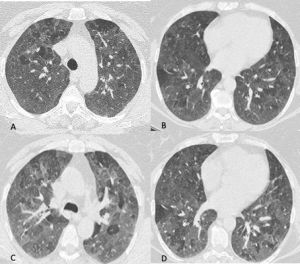

Figura 2: Uomo di 41 anni con infezione da virus dell’Influenza A, giunge al Pronto Soccorso con febbre, tosse, malessere e lieve dispnea. La TCAR eseguita all’ingresso mostra nelle scansioni assiali (A-B) e nella ricostruzione MPR coronale (C) la presenza di sfumati micronoduli centrolobulari nel lobo superiore destro e nel lobo medio e di aree di aumentata densità con aspetto in parte a "vetro smerigliato" ed in parte consolidativo nel lobo inferiore destro.

Figura 4: Donna di 78 anni con diagnosi di Linfoma di Hodgkin. Le immagini assiali (A-B-C) mostrano il parenchima polmonare normale. Un anno dopo la paziente giunge al Pronto Soccorso per un rapido peggioramento della funzionalità respiratoria, dispnea e tosse. La TCAR eseguita alcuni giorni dopo il ricovero nel reparto di Malattie Infettive (D-E-F) mostra la presenza in entrambi i polmoni di "vetro smerigliato" diffuso con relativo risparmio delle zone sub-pleuriche e la comparsa di formazioni pseudocistiche nel lobo superiore sinistro (frecce in D ed E). L’ipotesi formulata e poi confermata dal laboratorio è stata quella di polmonite da Pneumocystis Jirovecii.

L’agente patogeno più comune è il virus dell’influenza e i segni e i sintomi clinici come anche i reperti di imaging variano a seconda dello stato immunitario dell’ospite. I pattern in TCAR sono molteplici: “vetro smerigliato” e consolidazione; sfumati noduli e micronoduli centrolobulari alcuni con aspetto ad “albero in fiore”; ispessimento dei setti inter ed intralobulari ed ispessimento delle pareti bronchiali (Figura 2). Ingrandimento dei linfonodi mediastinici e versamento pleurico possono essere presenti, sono invece reperti rari nella polmonite da COVID-19.

Le polmoniti virali che si manifestano con “vetro smerigliato” diffuso sono quella causate da Citomegalovirus (Figura 3), da herpes simplex virus e da virus della varicella-zoster.